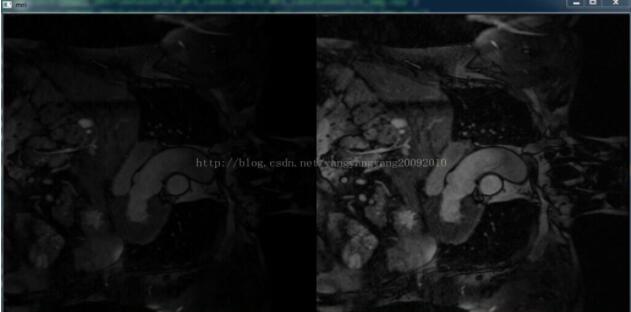

cv2.imshow('mri', np.concatenate([temp,img], 1))

均衡化前、后对比效果